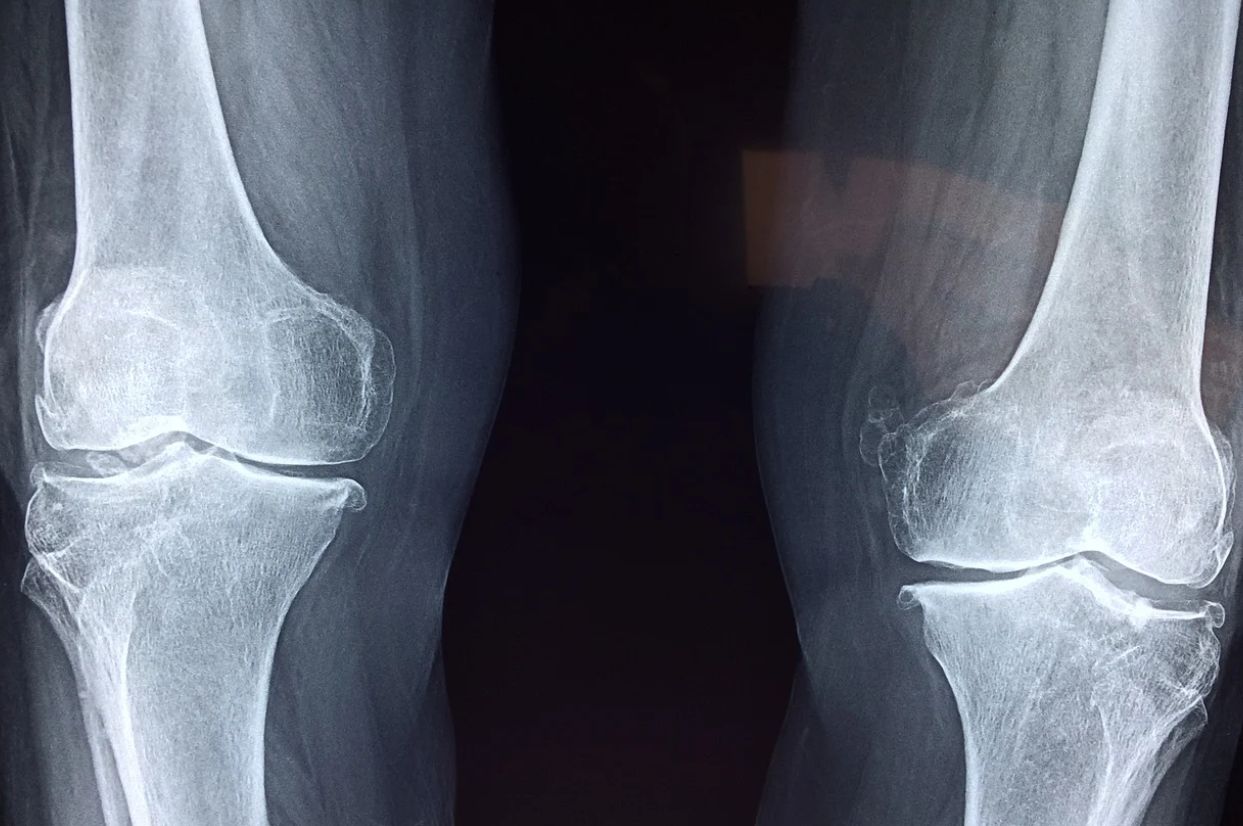

근골격계질환을 산업재해로 인정받으려면

근골격계질환으로 산업재해로 인정받으려면 질환과 작업과의 연관성이 있어야 한다. 작업과 연관있는 근골격계질환을 직업성 근골격계질환이라 말하기도 한다. 최근 10년간 전체 직업병환자 중 70%가 넘는 환자가 근골격계질환자이다. 직업병 중에서 가장 많은 빈도를 차지하는 질환이다. 그런데 신체적인 작업에 더해 정신적 요인까지 생각해 보면 예방이 가능한 질환이기도 하다.